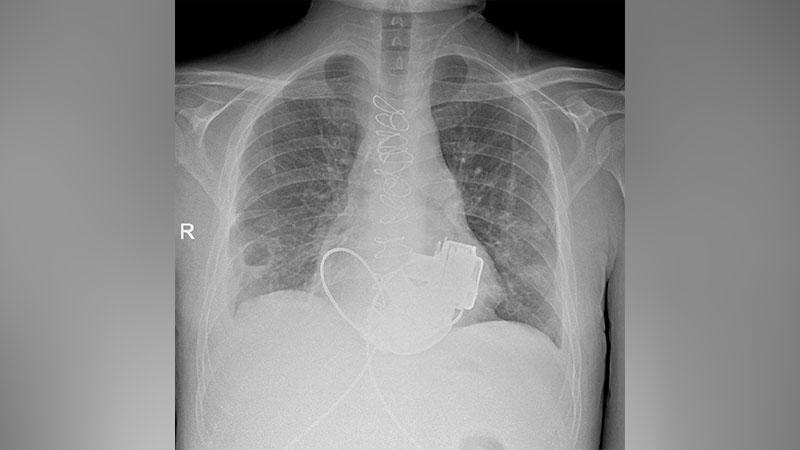

Главврач Игорь Реутский принял решение об имплантации двух искусственных желудочков, что является нестандартным решением, так как обычно устанавливается одно устройство. Операцию провела команда ведущих хирургов под руководством академика Геннадия Хубулавы в рамках программы губернатора Александра Беглова по лечению терминальной сердечной недостаточности. Это десятая подобная операция в больнице.

Антон успешно преодолел сложный послеоперационный период и теперь готовится к выписке. Он адаптировался к жизни с двумя имплантированными устройствами и с нетерпением ждёт возвращения в Мариинскую больницу, где ему предстоит трансплантация донорского сердца. Установка искусственных желудочков стала для него временным решением, позволяющим дождаться этой жизненно важной операции.